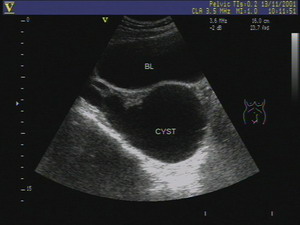

2、超声诊断:某些输卵管积水可以在超声上显示出来,但是超声只能提示有液性暗区而不能蕞终确诊是否有积水,多在验证的急性期显示出来,超声示子宫侧或者双侧出现不规则液性暗区,呈腊肠状,管内可见异常回声等。